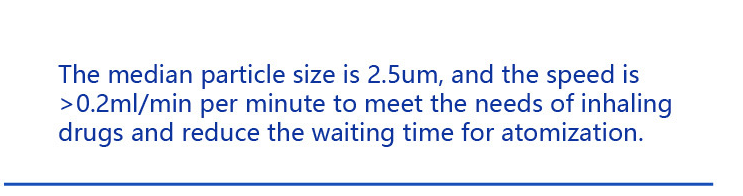

With its advanced micro-net technology, the nebulizer delivers medication in fine mist form, ensuring maximum absorption and effectiveness. Whether you are dealing with allergies, asthma, or other respiratory issues, this device will provide you with the relief you need.